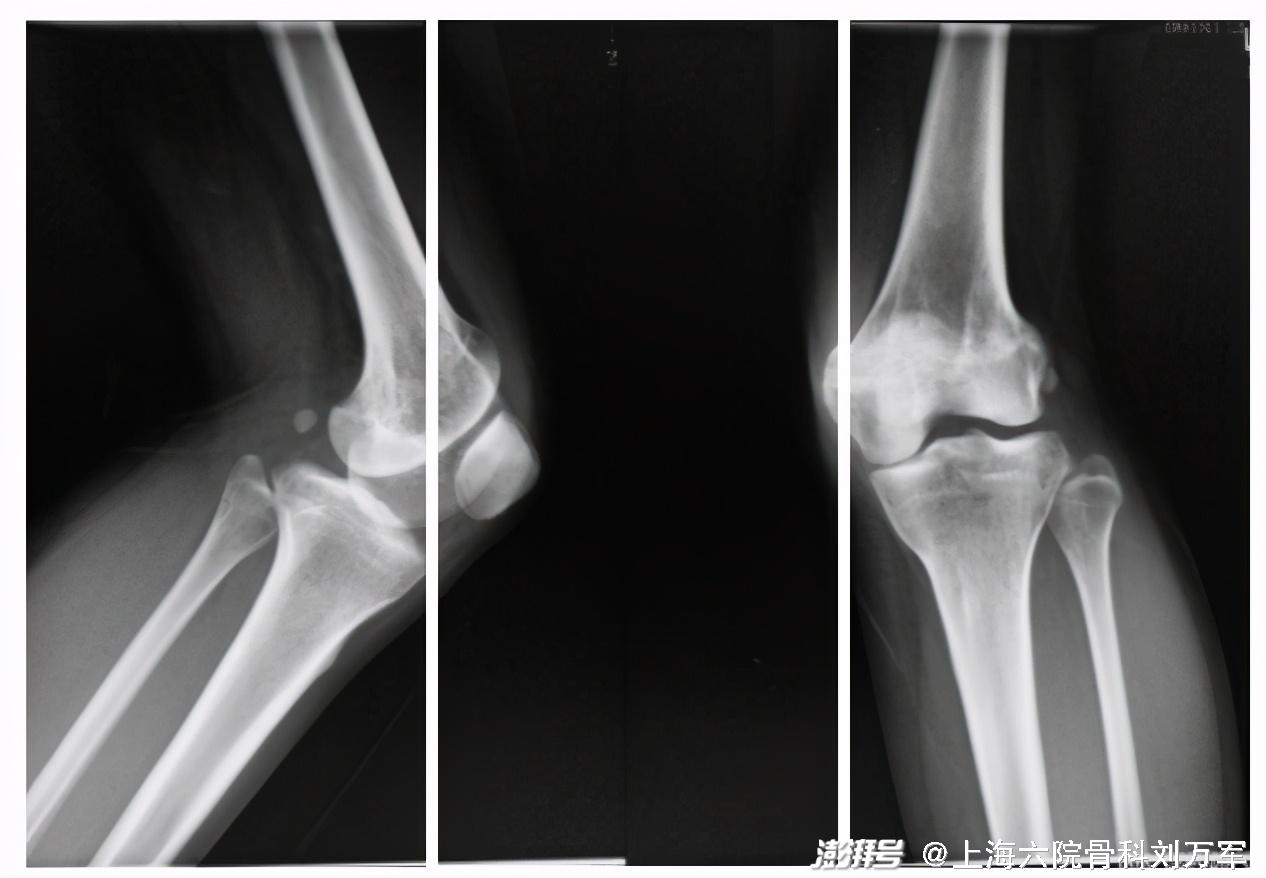

对于力线不良导致的轻中度单间室膝关节骨性关节炎,

截骨已成为有效的治疗手段。其中以矫正外翻膝为主的股骨远端截骨(DFO),治疗预后良好,受到患者广泛欢迎。

患者女性,32岁,3岁发现先天性髋关节发育不良(DDH),行石膏牵引。上小学后出现左侧膝关节严重外翻,但当时无疼痛不适的感觉所以并没有在意。24岁时摔了一跤导致髋关节脱位,在附近医院做了髋关节置换术。

刘主任仔细检查了患者病情,认为长期膝外翻已并发局部的膝关节骨性关节炎,建议行左下肢股骨下端截骨术,保膝不置换。

DFO截骨手术是通过纠正下肢力线来重新均衡内外间室的载荷,从而达到缓解疼痛,重建关节功能的目的。